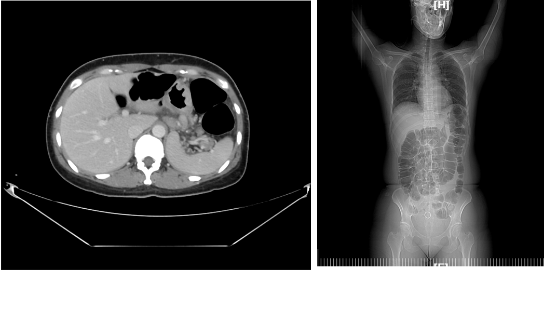

基本情况:女性,42岁,因“大便变细,腹胀伴呕吐”于2014-4-5至我院就诊。查胃镜示:低分化腺癌,CT示:胃癌并盆底种植、肠梗阻胃癌并盆底种植,胃周淋巴结转移,不完全性梗阻,左侧输尿管受累并近端泌尿系轻度积水扩张。为了解除梗阻,于2014-4-8予行剖腹探查术,术中见肿瘤种植至盆腔致冰冻骨盆,遂予行乙状结肠造瘘术,并行腹腔结节活检。术后病理提示:胃低分化腺癌,HER2(+++),CK20(+),CK7(+),CDX2(+),CEA(+),术后恢复良好。

影像学检查:

该患者入组了徐瑞华院长主持的赫赛汀治疗晚期胃癌的研究,于2014-4-18至2014-7-15行赫赛汀300mg+多西他赛90mg+希罗达1.5 bid×14d q3w方案化疗第1-6程,第2、4、6程复查CT,疗效评估:PR。腹痛腹胀明显缓解,胃纳、大便正常。毒性可耐受,1°脱发、2°粒缺。2014-8-4至2015-08-25行予赫赛汀400mg+希罗达1.5 bid×14d q3w方案维持化疗第1-16程,每6周复查CT(平扫或增强)、每12周复查心脏彩超。PFS:17.2月。